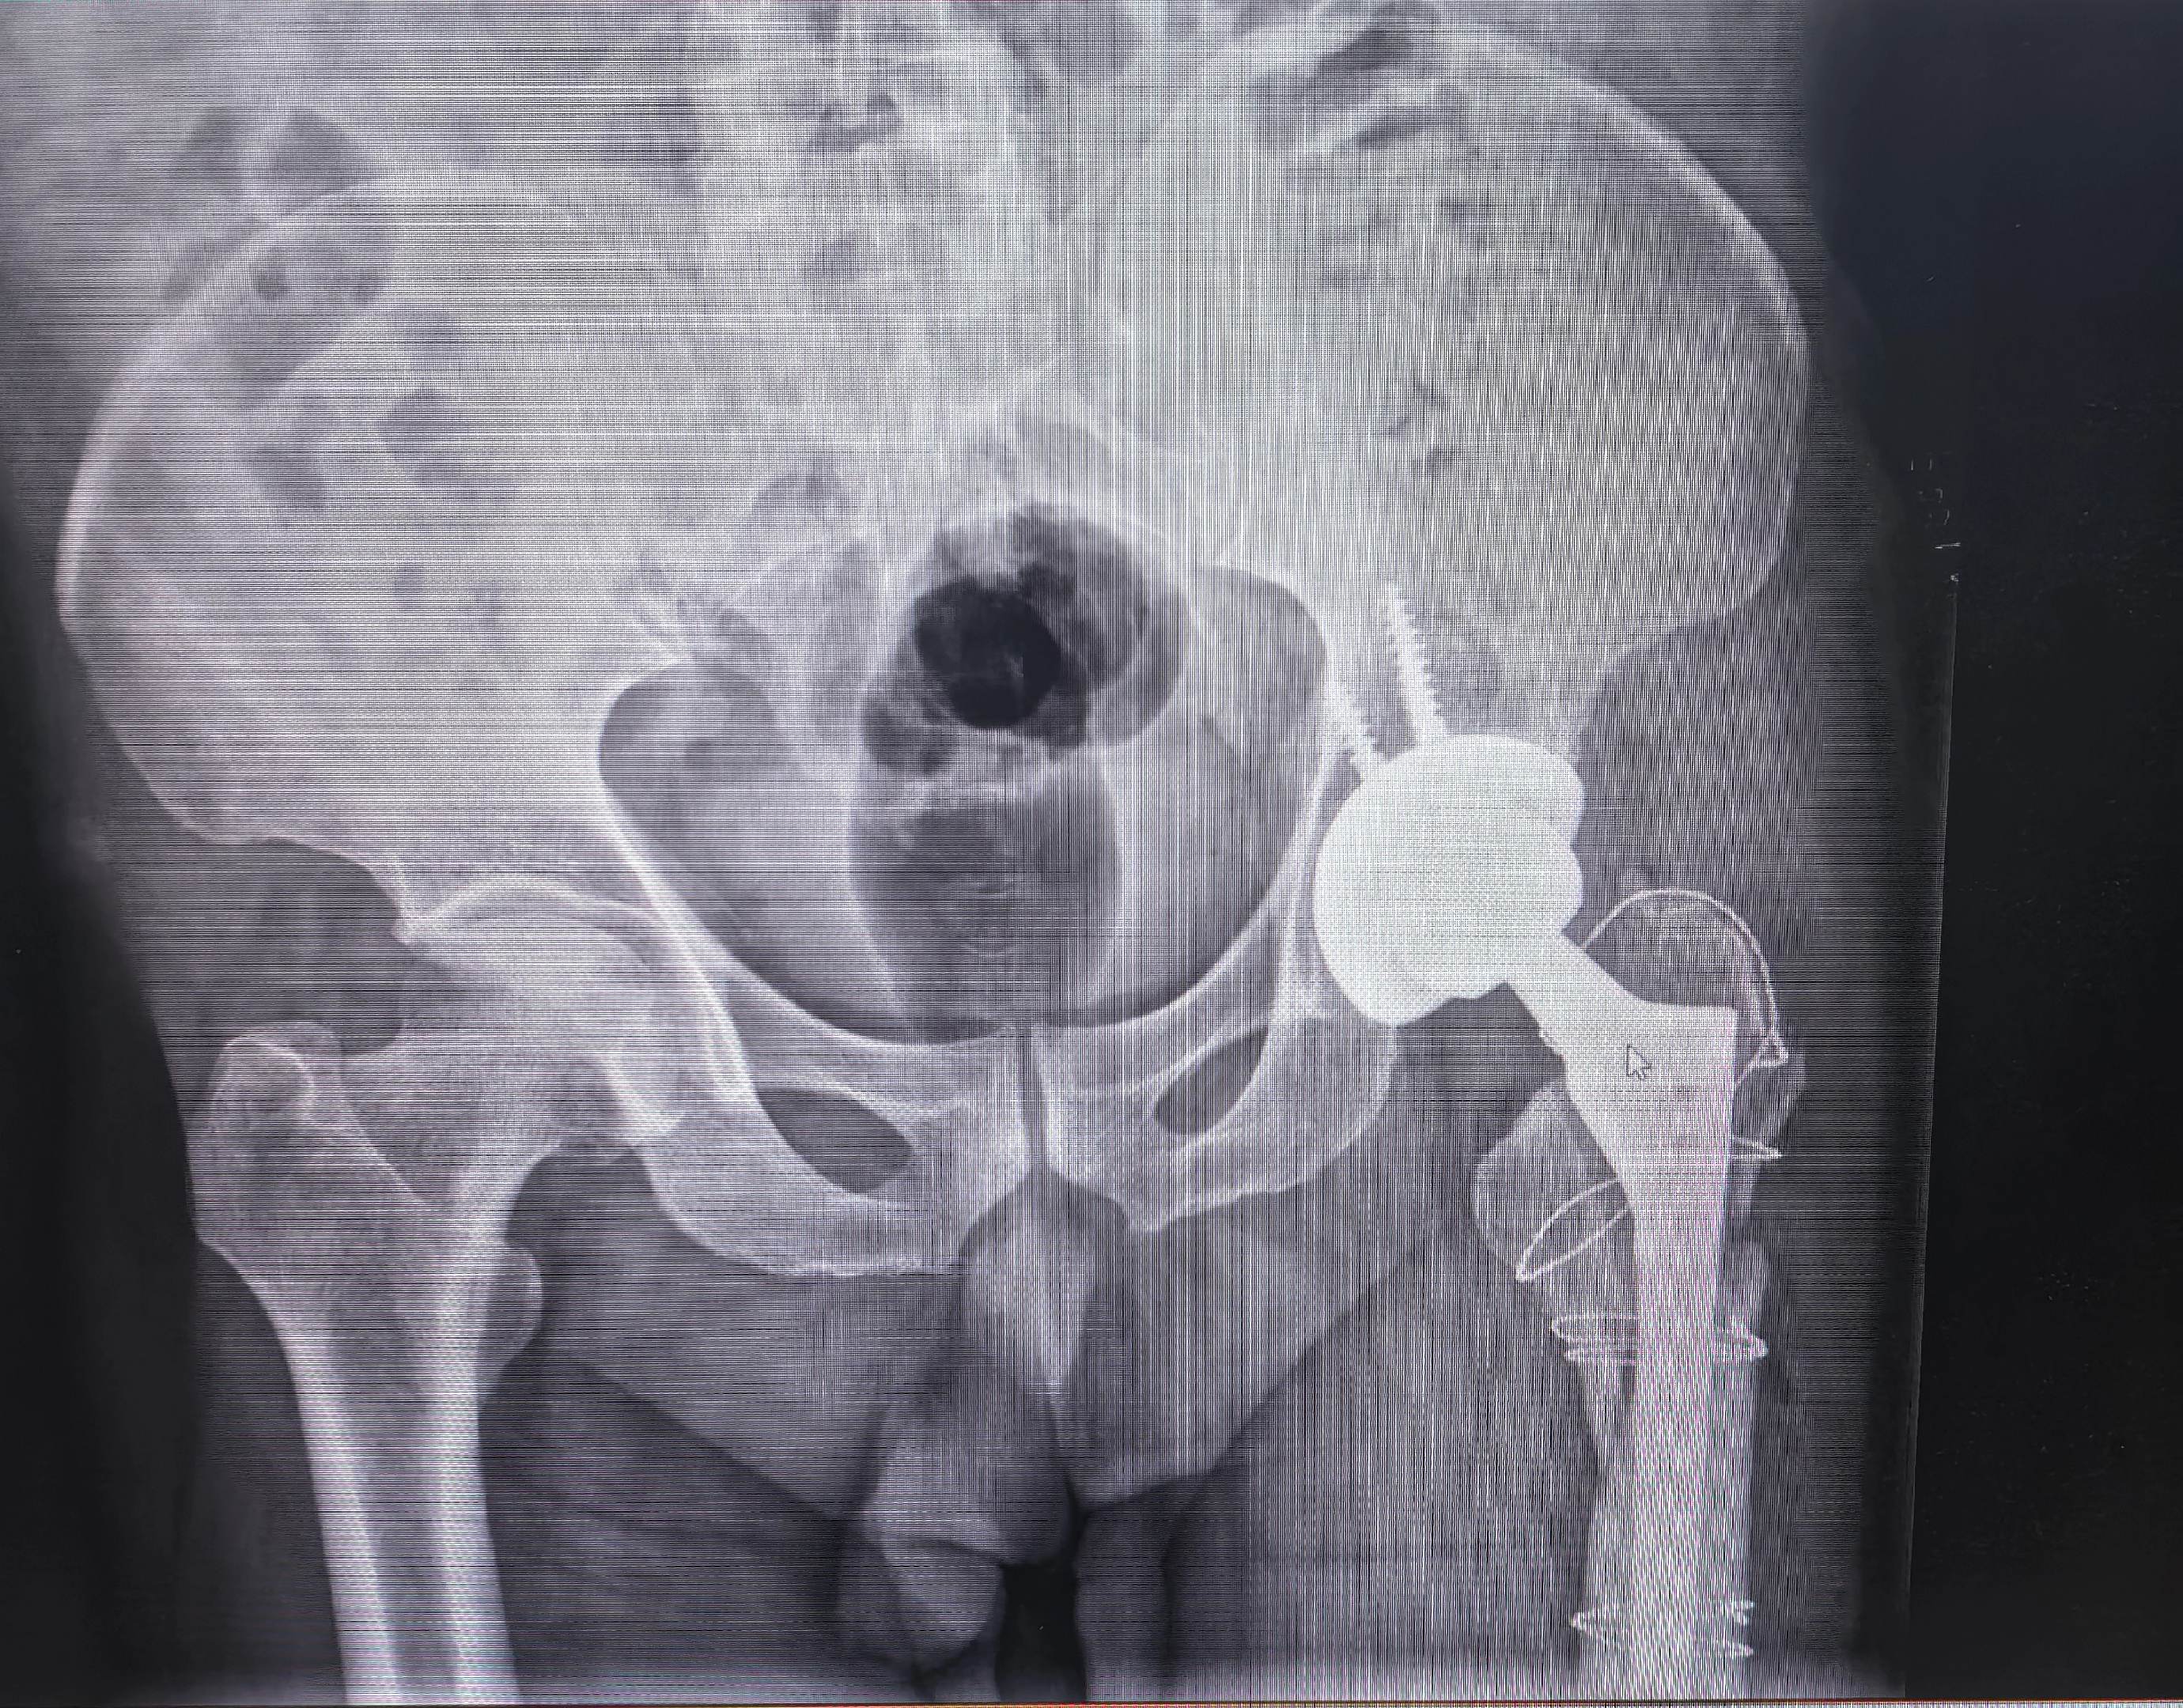

髋关节置换术后假体周围骨折。老年人一定要重视骨质疏松的预防(抗骨质疏松、适当运动、防跌倒),避免出现假体周围骨折的情况,虽然可以手术治疗,两天后也可以下床,但是创伤要比第一次大。